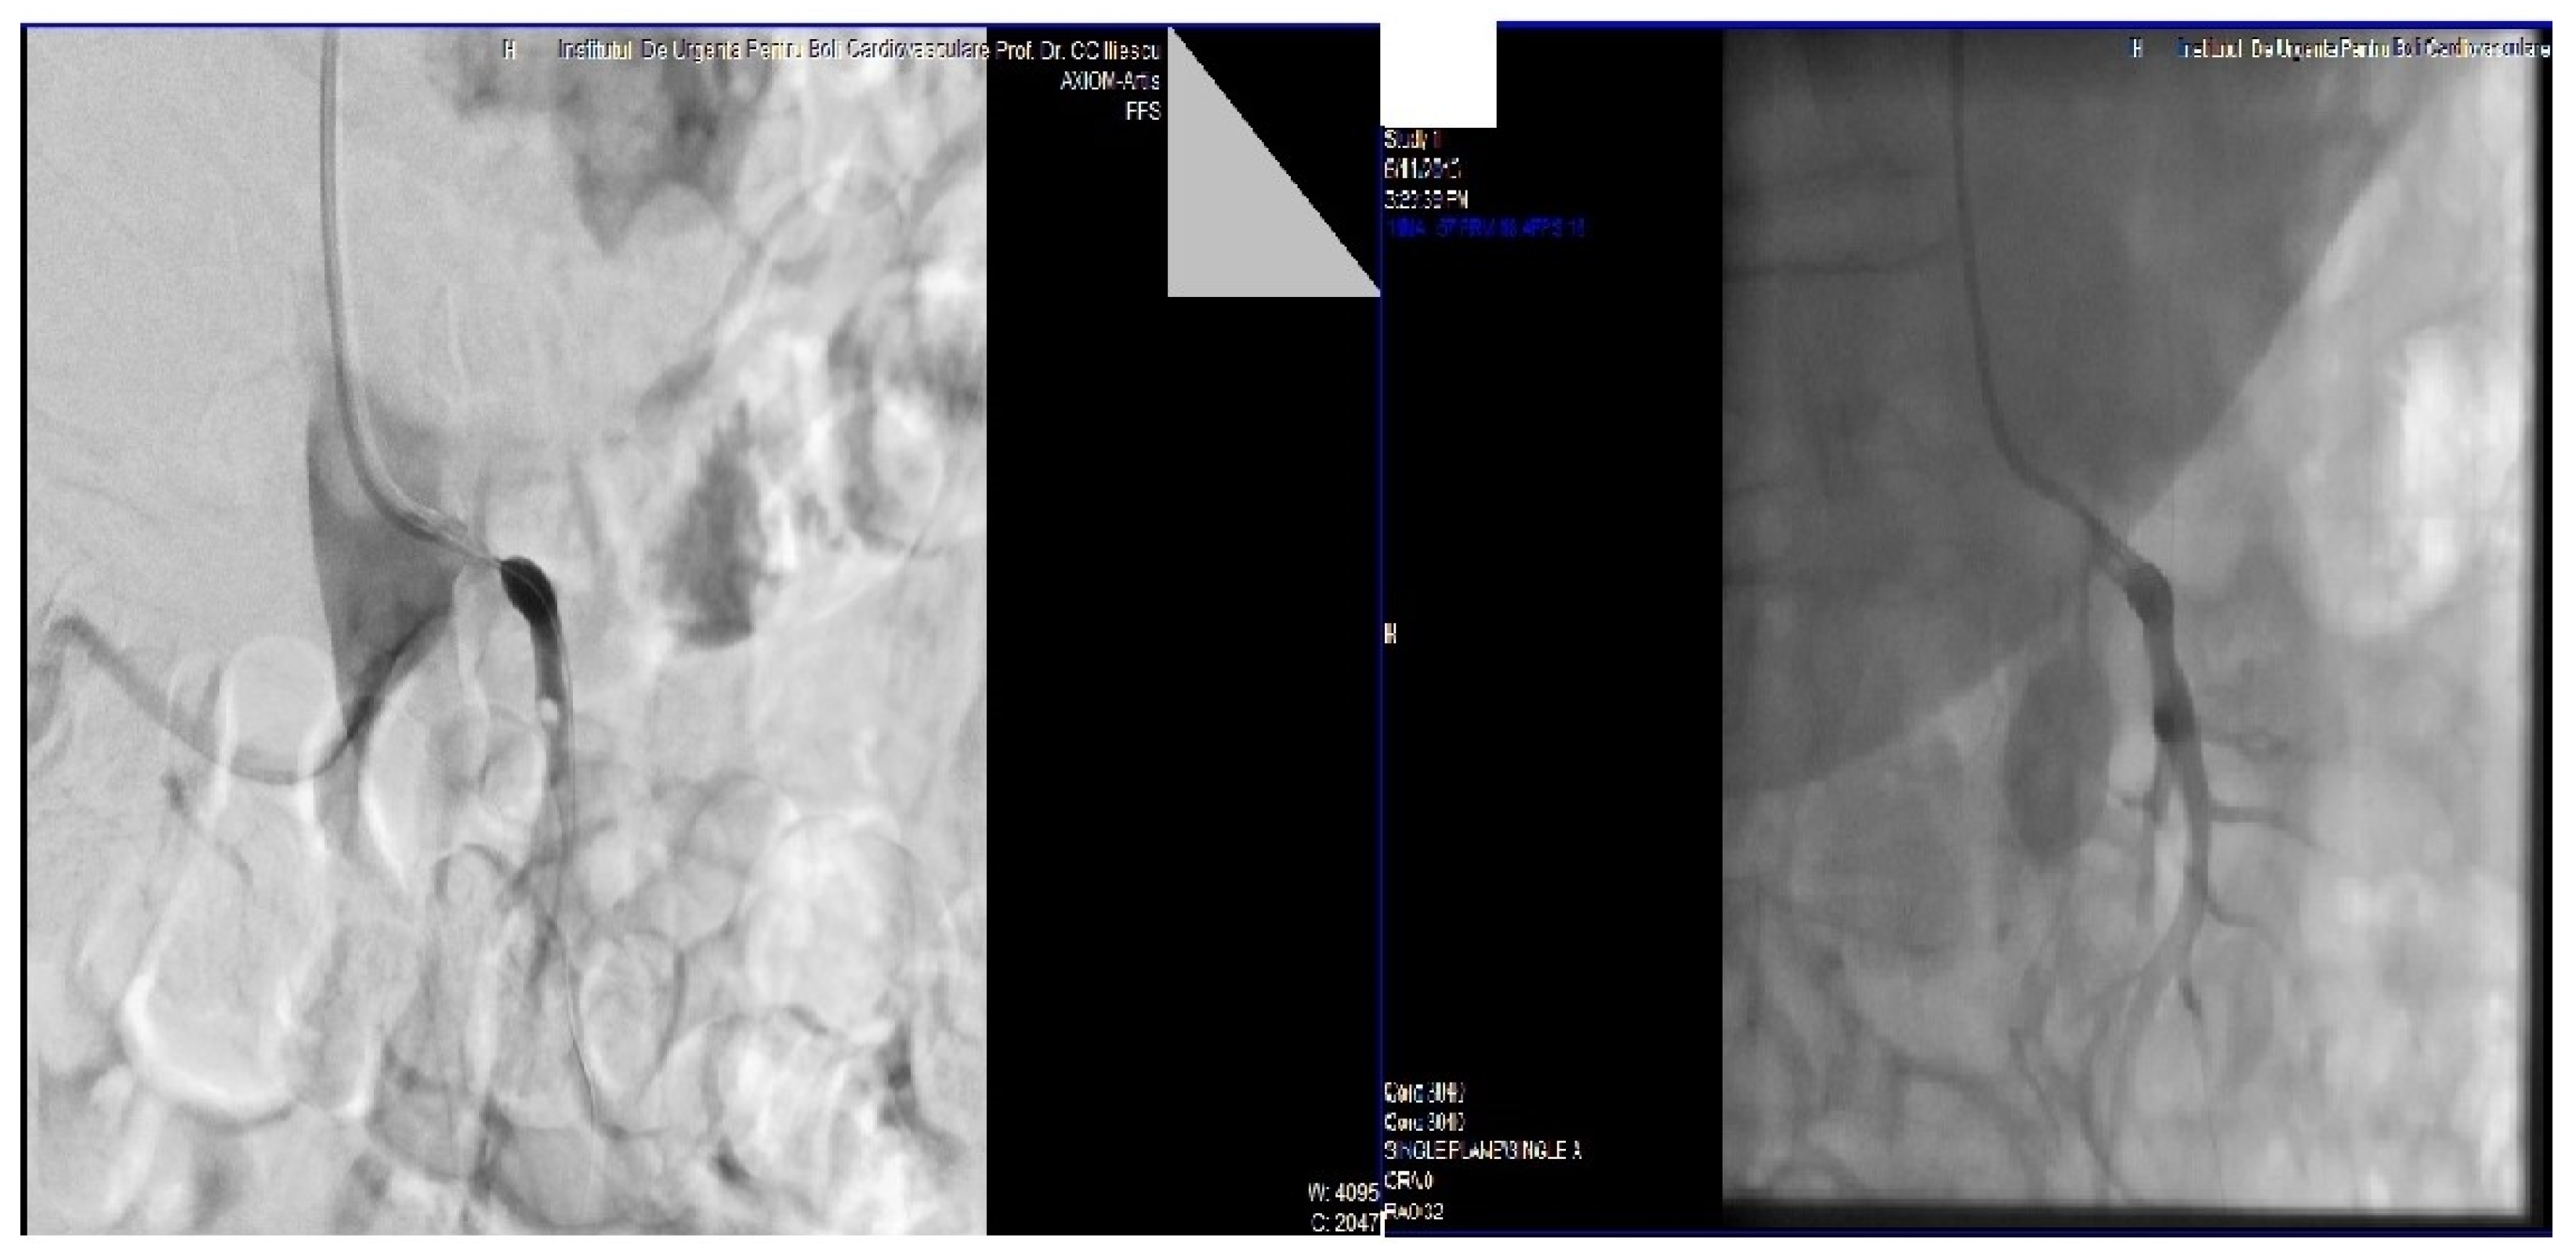

2. Case Presentation